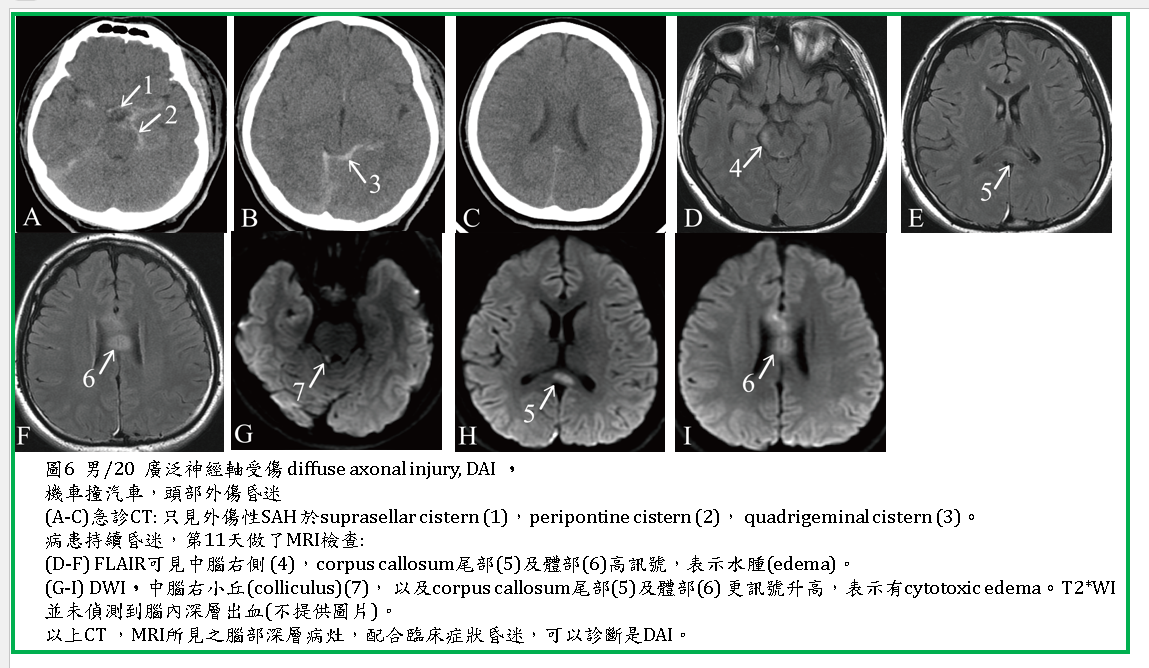

廣泛神經軸受傷(diffuse axonal injury):

Diffuse axonal injury(DAI)又稱為撕裂性外傷(shearing injury)。如果臨床上病人的症狀很嚴重,尤其是昏迷,而CT並無明顯的血塊或腦水腫等與臨床症狀相配合的病灶時,就應懷疑是DAI。DAI在CT的診斷率較低。MRI診斷率較高,但也只是看到腦內深層一些小病灶,再配合臨床症狀,而推測病患有DAI (圖6) 。

CT:看到點狀出血或小區域腦水腫,尤其在大小腦的深層,如胼胝體、基底核、腦幹、灰白質交接處。有些只看到一些SAH, IVH, 可做為佐證.

MRI:T1WI,與CT相同,尋找到上述區域的小血塊,FLAIR及T2WI較敏感,可看到高訊號小病灶,代表腦水腫或出血。DAI引起腦內深層小水腫(圖6) ,在DWI呈現高訊號,代表是一種cytotoxic edema。T2*WI 或SWAN 更是必要的波序,它可以偵測到更多腦內的深層小出血,提高對DAI的診斷率。